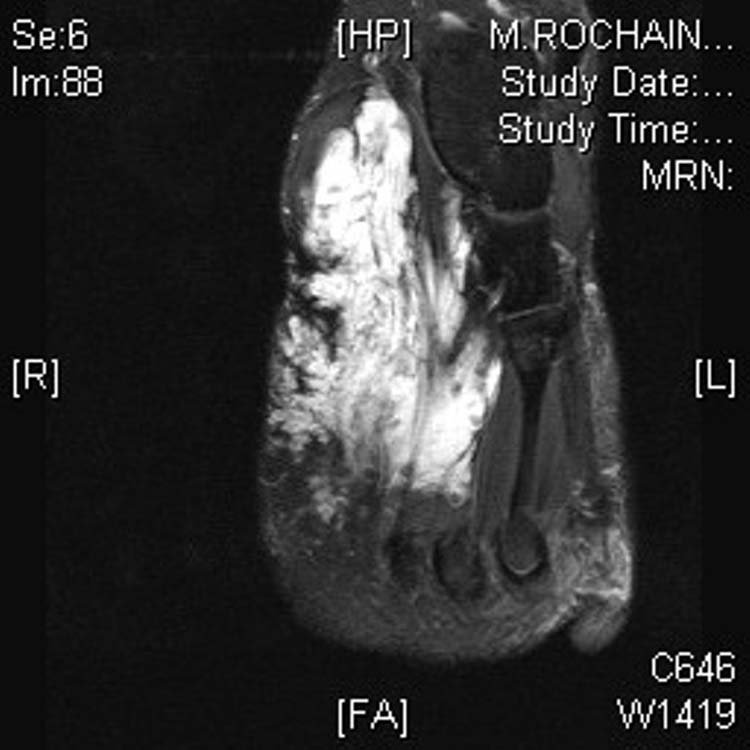

MRI of the right foot shows diffuse soft tissue swelling with mild Plantar Foot Lesions Radiology The aim of this review is to provide the reader with a comprehensive overview of the magnetic resonance imaging (mri) characteristics of the. The purpose of this pictorial review is to aid the clinician in distinguishing different benign lesions within the foot and ankle. This review considers imaging features of palpable lesions around the foot that are generally benign. Soft. Plantar Foot Lesions Radiology.